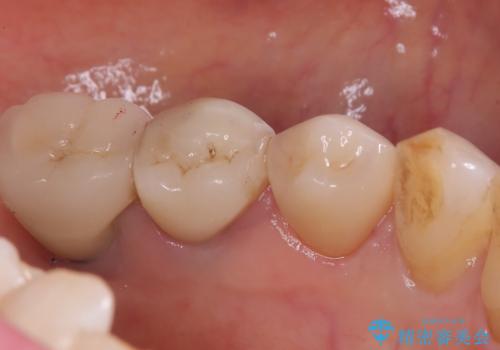

- 主訴:歯茎付近の知覚過敏が強くてどうにかしてほしい

左下4番目の歯の歯頚部に強い知覚過敏症状が出ており、沁み止め材の塗布では症状緩和が望めない状態でしたので、セラミッククラウンで覆う処置としました。